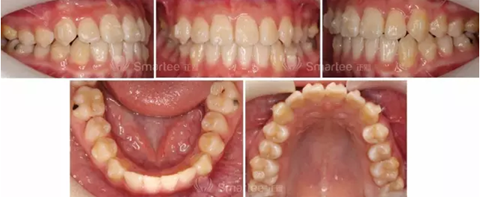

(矯治2個(gè)月)

(矯治5個(gè)月)

(矯治12個(gè)月,第一次精調(diào))

(矯治14個(gè)月,第一次精調(diào)2個(gè)月)